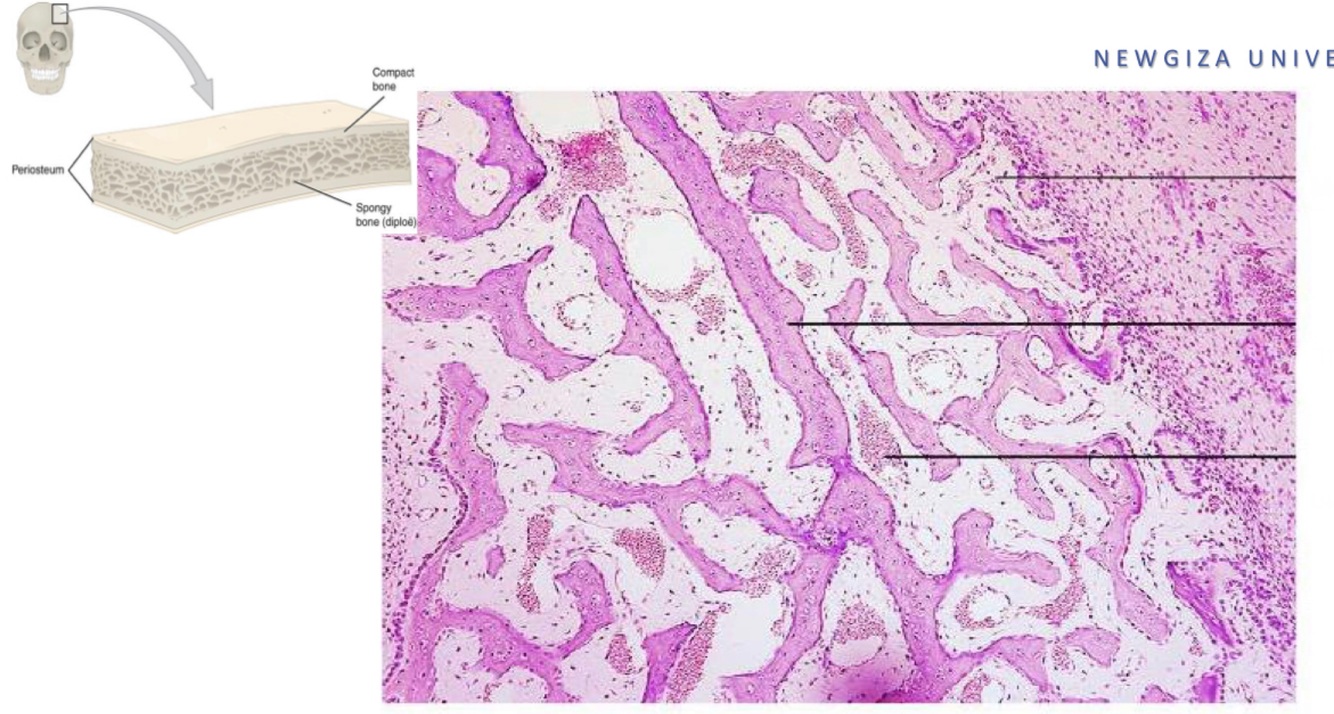

which is wooven and lamelar bone ?

Bone microscopy of Osteogenesis imperfect-a patient ; describe.